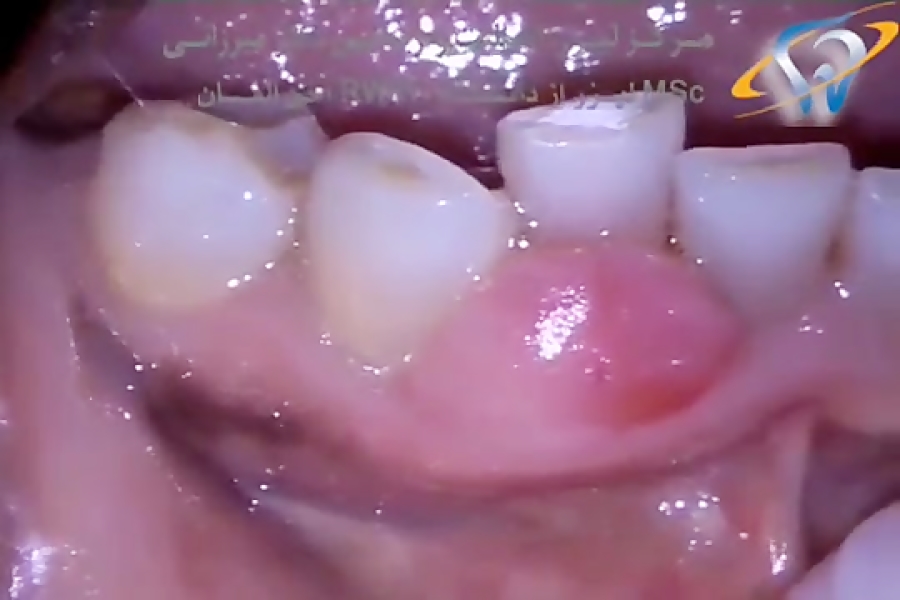

From www.aparat.com

MD Epulis Removal Epulis Removal Dental Code Epulis fissuratum, epulis granulomatosum, congenital epulis, pregnancy epulis, giant cell epulis and ossifying fibroid epulis. Answered on september 15, 2012. The definitive treatment for any epulis is surgical excision. the purpose of this article is to present a case demonstrating the treatment of epulis fissuratum due to a poorly adapted prosthesis using a single surgical procedure involving conventional excision. Epulis Removal Dental Code.